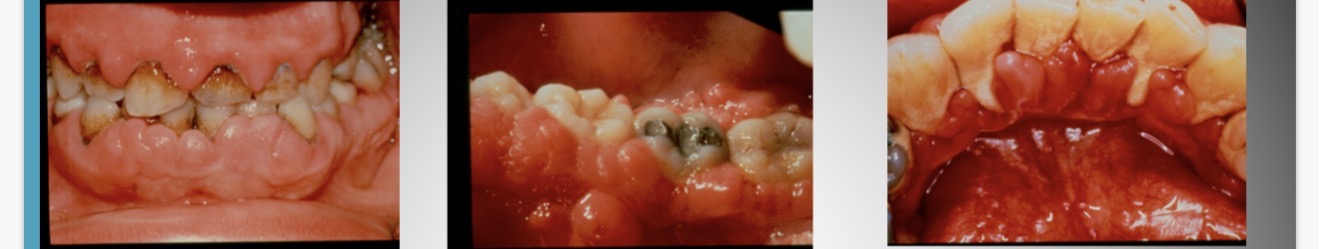

Condition?

Drug induced gingival enlargement

What drugs can cause gingival enlargement?

cyclosporine (SandimmuneĀ®)

dilitiazem (CardizemĀ®)

nifedipine (Procardia)

diphenylhydantoin (DilantinĀ®)